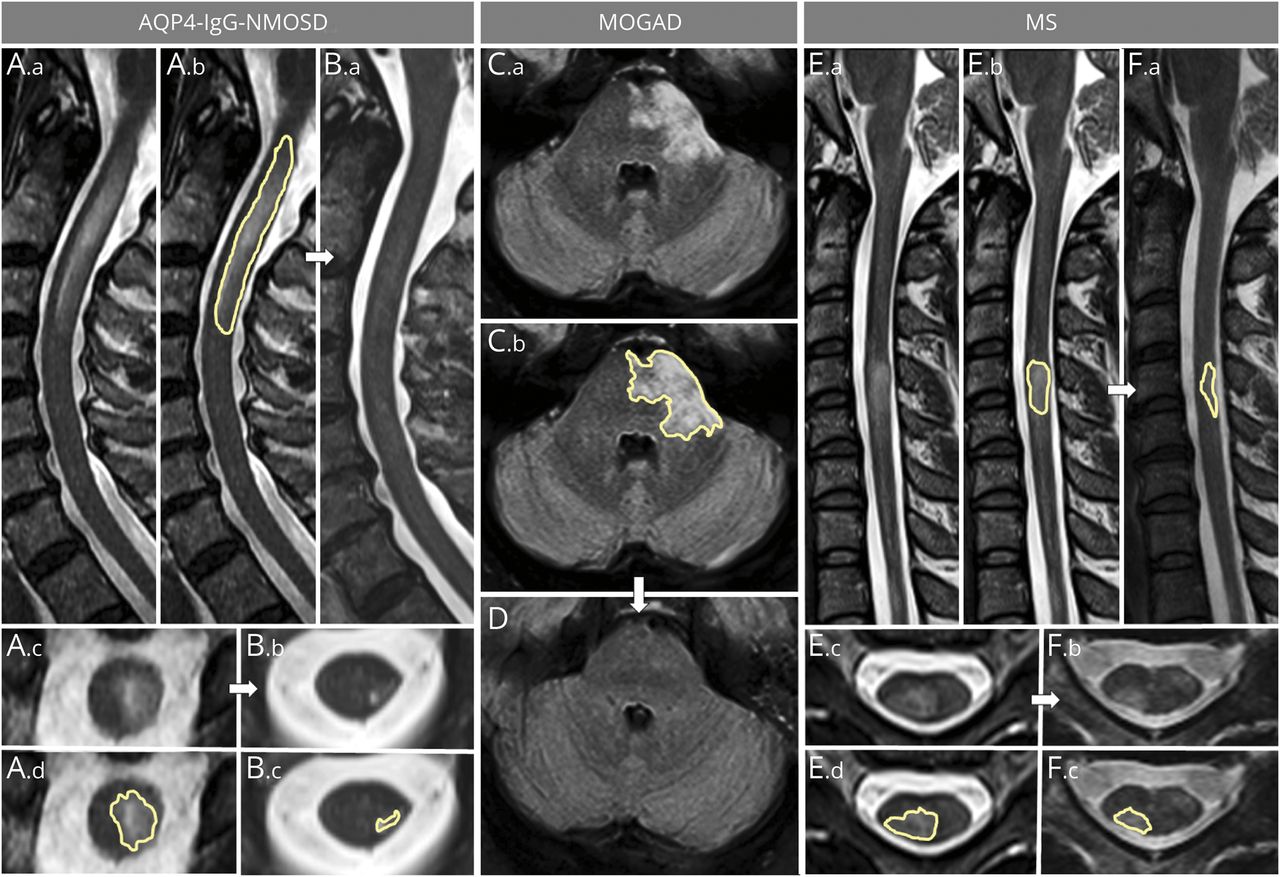

左边的图中显示矢状(的一部分。一个。b, b。a) and axial (A.c, B.b) T2-weighted images of a longitudinally extensive spinal cord lesion associated with aquaporin 4–immunoglobulin G–positive neuromyelitis optica spectrum disorder (AQP4-IgG-NMOSD) acutely (A) and at follow-up (B). The largest acute axial area of the lesion was manually outlined acutely on sagittal (A.b, yellow outline) and axial (A.d, yellow outline) images and at follow-up (B.c) to determine lesion resolution/reduction. In the center of the figure, an acute brainstem T2-hyperintense lesion associated with myelin oligodendrocyte glycoprotein–immunoglobulin G–associated disorder (MOGAD) is shown on axial fluid-attenuated inversion recovery images (C.a). The largest axial T2 lesion area manually outlined acutely (C.b, yellow outline) resolves to undetectable at follow-up MRI (D). On the right, a multiple sclerosis (MS) myelitis T2-hyperintense lesion is shown (E.a, E.b) with the largest area of the T2-hyperintense lesion outlined acutely on both sagittal (E.b, yellow outline) and axial (E.d, yellow outline) images. Despite being smaller acutely compared to the lesions associated with AQP4-IgG-NMOSD and MOGAD, the MS lesion only shows moderate reduction in size at follow-up, where it is still clearly visible on both sagittal (F.a, yellow outline) and axial (F.b, F.c, yellow outline) images.